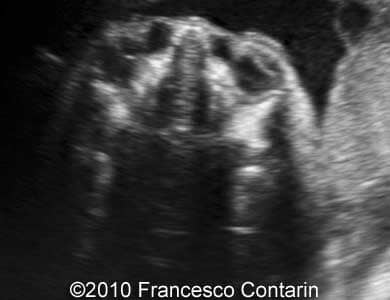

This is a case of a 30-year-old G1 P0 who was scanned at 29 weeks of gestation. We found a bilateral dacryocystocele.

Images 1,2: Transverse view of the bilateral dacryocystocele located medial to the orbits.